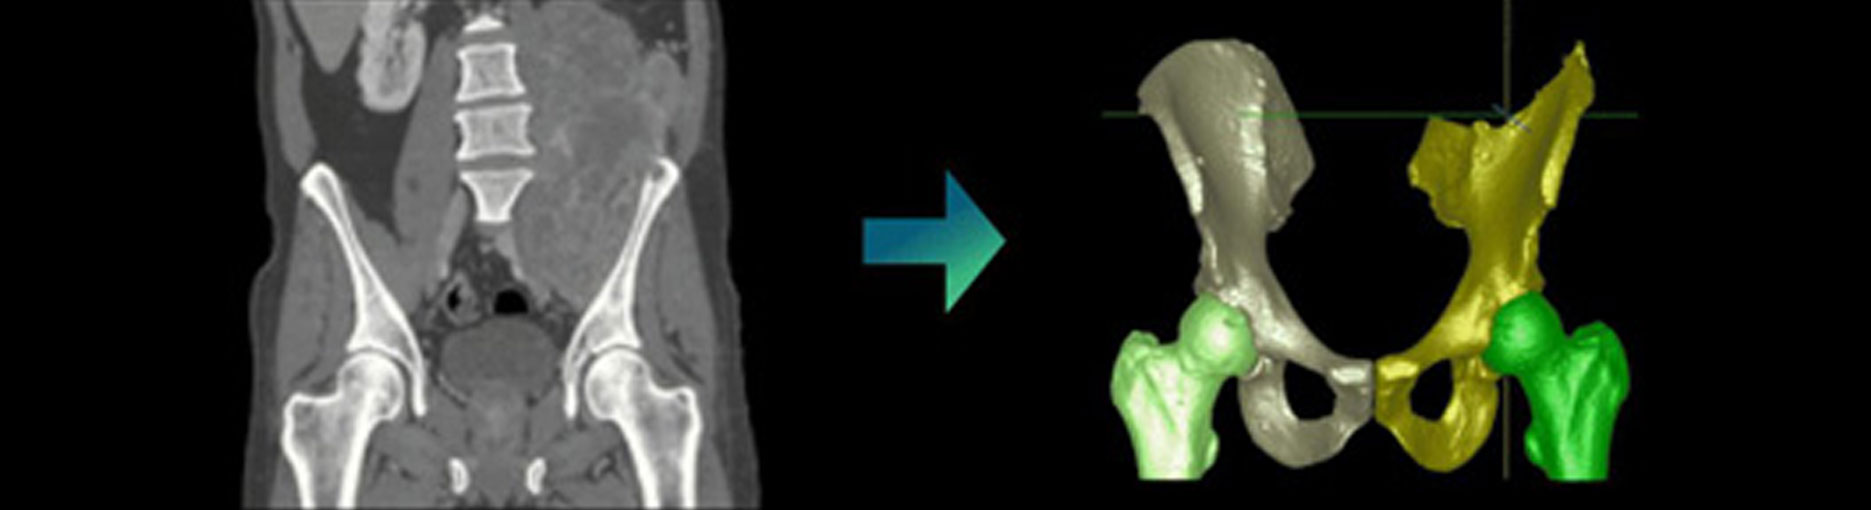

At Chimaera, we develop solutions that support the entire data-driven analysis process. Our offerings include precise annotations for AI training datasets, automated or semi-automated segmentations, and interactive 3D visualizations that allow clinical teams to intuitively explore complex structures. These tools provide a foundation for more reliable detection and quantification of pathological changes, including fat content determination, tumor segmentation, and volumetric analyses for surgical planning.